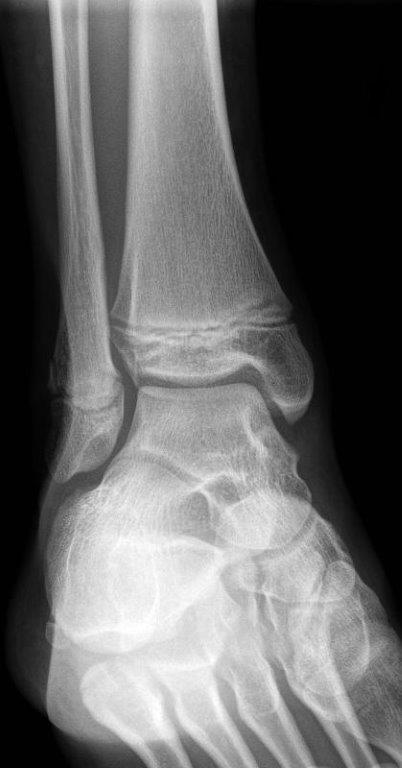

Avulsion fracture of base of fifth metatarsal

- If 4th and 5th inter-metatarsal joint involved (Jones Fracture), not suitable for CAM Boot.

Single and multiple non-displaced metatarsal fractures

- Follow up Orthopaedic fracture clinic in 7 - 10 days.